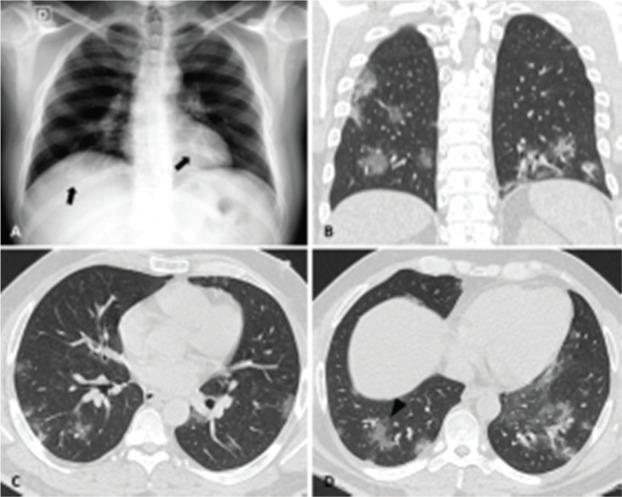

The coronavirus disease (COVID-19), caused by the severe acute respiratory syndrome coronavirus 2 (SARS-CoV-2), emerged in Wuhan city and was declared a pandemic in March 2020. Although the virus is not restricted to the lung parenchyma, the use of chest imaging in COVID-19 can be especially useful for patients with moderate to severe symptoms or comorbidities. This article aimed to demonstrate the chest imaging findings of COVID-19 on different modalities: chest radiography, computed tomography, and ultrasonography. In addition, it intended to review recommendations on imaging assessment of COVID-19 and to discuss the use of a structured chest computed tomography report. Chest radiography, despite being a low-cost and easily available method, has low sensitivity for screening patients. It can be useful in monitoring hospitalized patients, especially for the evaluation of complications such as pneumothorax and pleural effusion. Chest computed tomography, despite being highly sensitive, has a low specificity, and hence cannot replace the reference diagnostic test (reverse transcription polymerase chain reaction). To facilitate the confection and reduce the variability of radiological reports, some standardizations with structured reports have been proposed. Among the available classifications, it is possible to divide the radiological findings into typical, indeterminate, atypical, and negative findings. The structured report can also contain an estimate of the extent of lung involvement (e.g., more or less than 50% of the lung parenchyma). Pulmonary ultrasonography can also be an auxiliary method, especially for monitoring hospitalized patients in intensive care units, where transfer to a tomography scanner is difficult.